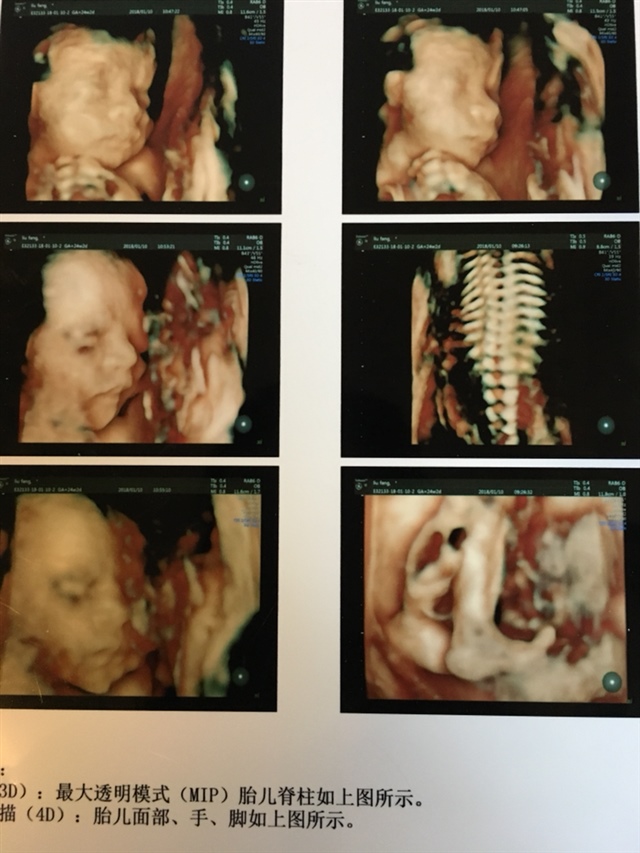

调皮的小家伙

好淘气~

哈哈!就是,医生说小家伙一点都不配合😄